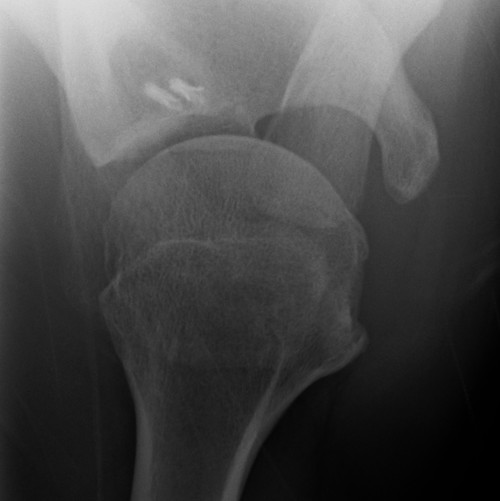

Case 2

Recurrent instability

- non recognised bony defect

- revised with Latarjet